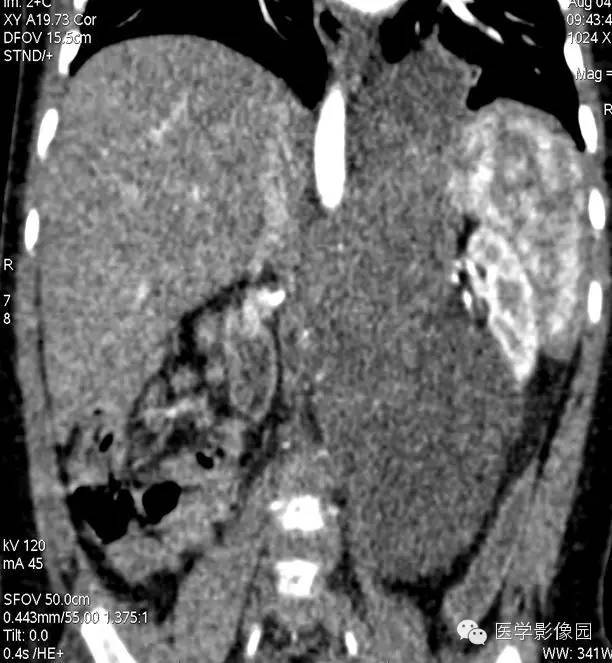

6——增强冠状位重建

7——增强冠状位重建